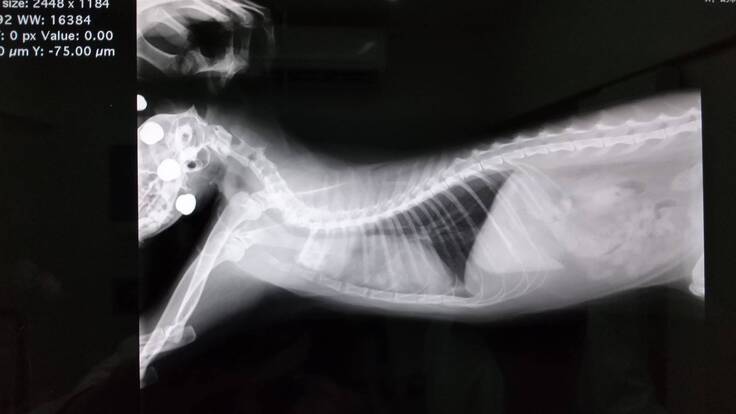

1年くらいすごく元気に楽しく暮らしていたのですが、2020年12月29日の夜中に体調が悪そうにしていました。年末だったこともあり、掛かりつけの病院がお休みだったので、診てもらえる別の病院を探しました。2020年12月30日急にぽんちゃんの呼吸が荒くなり苦しそうにしていて、朝一番で受診しました。胸水が溜まってて危ない状態でした。レントゲンを撮ったら肺が真っ白で300mlくらい水が溜まっていてぬいてもらいました。その日はICUに入って退院になりました。胸水が溜まった原因がFIP(猫伝染性腹膜炎)か悪性リンパ腫と言われました。年末休みに入っていたので検査センターに出す事ができずステロイドの内服薬をもらいました。

2021年1月7日胸水が溜まってないかレントゲンを撮ってもらい少し溜まっているが、抜くまでにはなりませんでした。胸のレントゲンを見せてもらったら通常の子より胸のほとんどが真っ白で治療をしないと後2ヶ月も生きられないと言われました。

初めての抗がん剤治療1月8日最初の抗がん剤治療のときのレントゲン写真です。真ん中の白くなっている部分が腫瘍です。この日からぽんちゃんの抗がん剤治療が始まりました。2ヶ月間は2種類の抗がん剤を週に1回投与します。初めての抗がん剤治療なので1日入院になり、胸水も溜まっていて溜まると呼吸困難になるので抜いてもらいました。2種類の抗がん剤治療をしたので胃と腸と骨髄に副作用が強く出てしまい、食欲が全くなくなってしまいましたので、3日間点滴に通いました。1回目の抗がん剤治療の経過です。

毛は抜けてしまった部分はまだ全然生えてきてませんが、2ヶ月もたないと宣告されていたぽんちゃんも3月中旬現在も生きている事がすごく嬉しいです。レントゲンの写真を見てもわかるように最初の頃の、白かった胸の部分もかなり良くなってきてます(^-^)